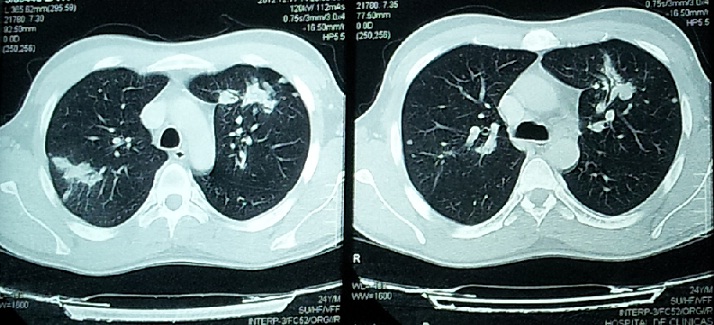

Un año después (a los 25 años) consulta por dolor dorso-lumbar de varios meses de evolución, asociado a hiporexia y pérdida de peso. Se decide su internación para estudio, con hallazgo en Rx de tórax de imágenes nodulares múltiples en ambos campos pulmonares, las cuales se analizaron luego con TAC de tórax. (Figura 1)

Figura 1. Tomografía computada de tórax: múltiples opacidades focales de bordes irregulares de afectación peribroncovascular de aspecto pseudocavitado